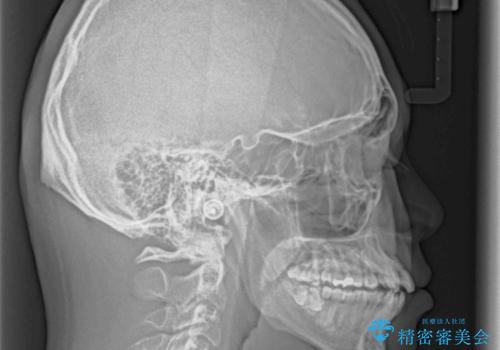

上下左右の犬歯が八重歯になっており、口元にもやや突出感があるため、上下左右の小臼歯4本を抜歯し、ワイヤー装置にて矯正治療を行うこととしました。

右上第一小臼歯は歯根癒着により移動せず、左上第二小臼歯は移動はするものの非常に動きが鈍かったため、抜歯したスペースを閉じるまでに非常に時間がかかってしまいました。